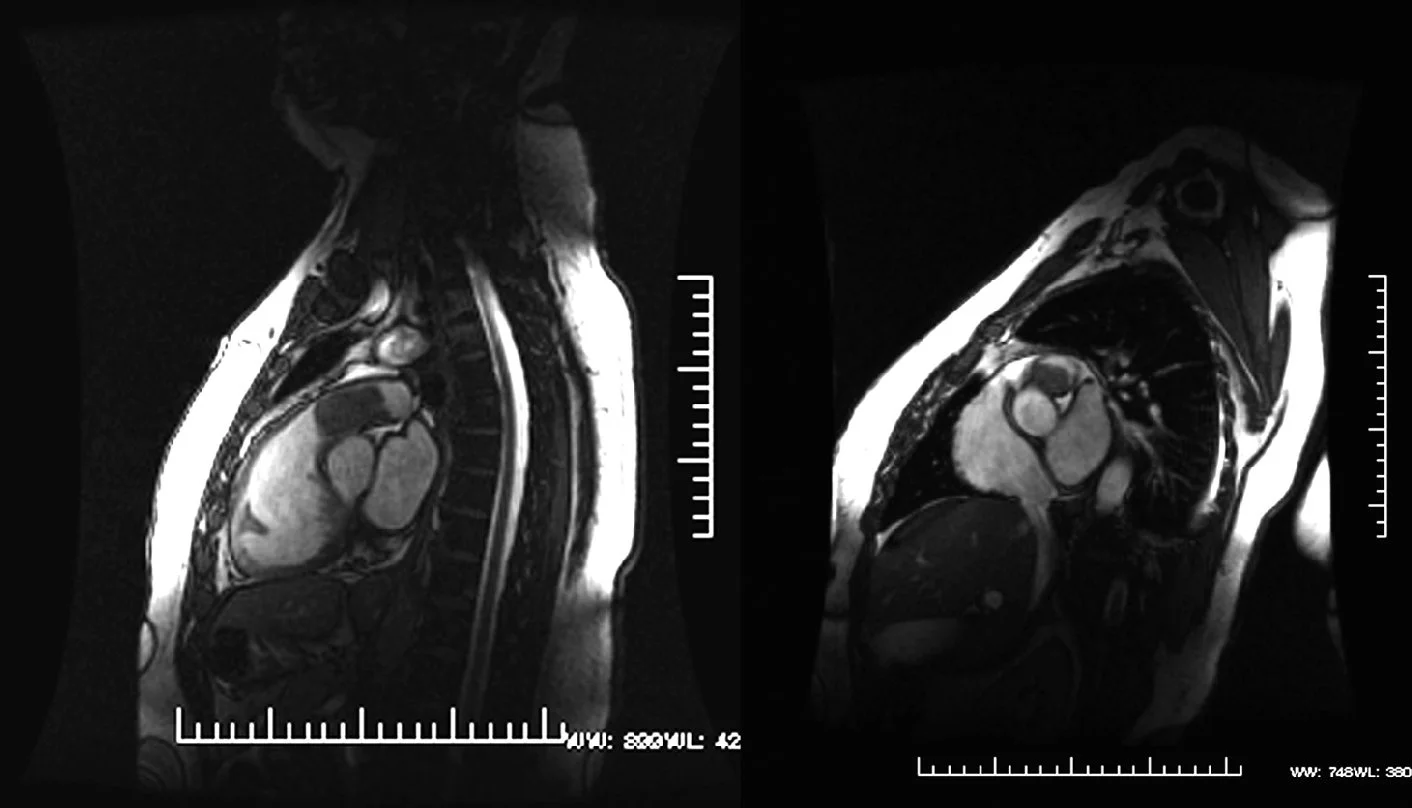

El sarcoma pulmonar primario (SPP) es una entidad tumoral pulmonar muy infrecuente, descrita en pocos casos e integrada por las variedades del angiosarcoma, leiomiosarcoma, rabdomiosarcoma, la variante sarcomatosa del mesotelioma y el sarcoma primario de Ewing/tumor neuroectodérmico primitivo de pulmón, que deben diferenciarse de las metástasis pulmonares de los sarcomas extratorácicos. Las técnicas radiológicas (tomografía computarizada y resonancia magnética) tratan de definir el origen de los tumores, la relación con estructuras vecinas y la invasión de éstas.

Presentamos el caso de un varón de 61 años, fumador, al que se descubrió, tras un cuadro catarral, una nodulación en el lóbulo inferior izquierdo en radiografías posteroanterior y lateral de tórax. Se realizó una tomografía computarizada de tórax sin contraste intravenoso que mostró una nodulación sólida y homogénea con ventana de mediastino, con bordes espiculados y signo de la “cola pleural”, con ventana de parénquima, como signos indicativos de malignidad. El diagnóstico anatomopatológico definitivo, tras lobectomía y linfadenectomía izquierda, fue de SPP de grado intermedio con patrón fusocelular y epiteloide, tipo histiocitoma fibroso maligno, que infiltraba la pleura visceral, en estadio pT2 N0; con positividad inmunohistoquímica para S-100, EMA (células epiteliales de conductos atrapados de la neoplasia), enolasa (células tumorales aisladas tipo epiteloide), Bcl-2, CD-34 y CK-pan (células epiteliales de conductos).